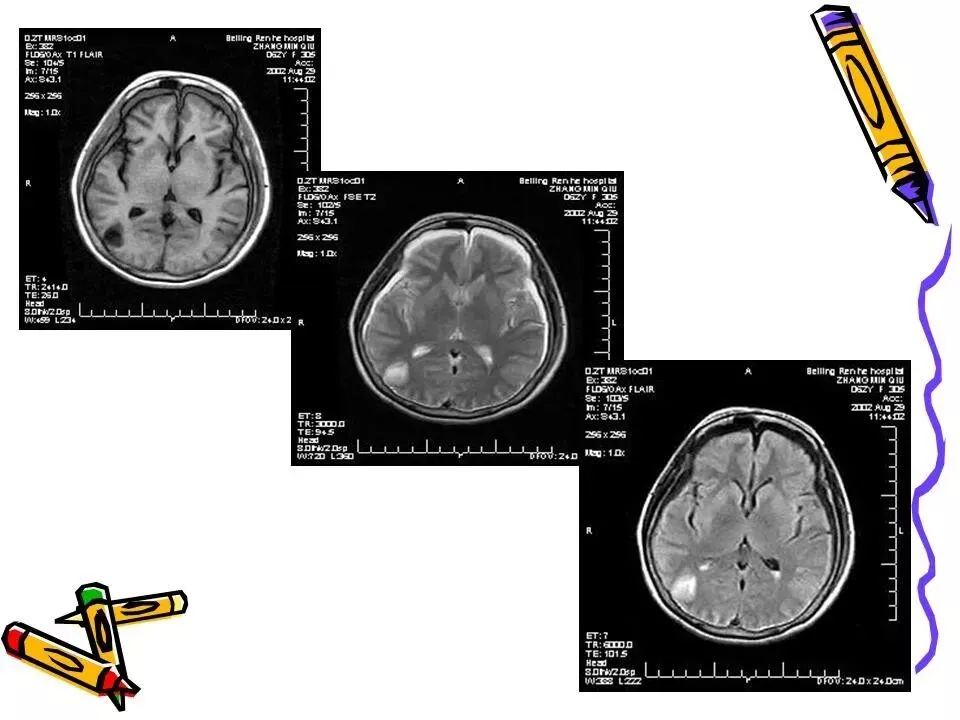

>常见颅脑外伤CT诊断(PPT)

常见颅脑外伤CT诊断(PPT)